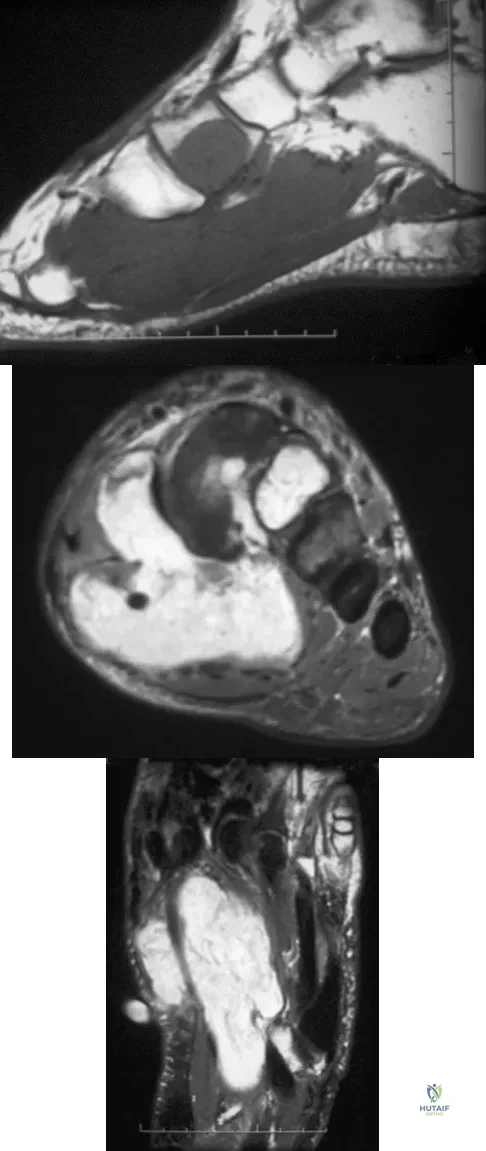

A 16-year-old girl has had hip pain for 1 year. Approximately 2 months ago she noted the development of a hard mass in the right buttock that has steadily increased in size. She now reports severe pain in the right buttock, with radiation down the leg and numbness involving the right foot and toes. A radiograph is shown in Figure 70a and an axial postcontrast T1-weighted MRI scan is shown in Figure 70b. A biopsy specimen is shown in Figure 70c. The chest CT shows multiple lung metastases. Treatment of this lesion should consist of

A 40-year-old man has a painless mass around his left ankle. He notes minimal growth over the past year. An MRI scan is shown in Figure 73a, and biopsy specimens are shown in Figures 73b and 73c. What is the most likely diagnosis?

A 13-year-old boy has had pain and swelling in his ankle for the past several months. Based on the radiograph, MRI scan, and biopsy specimen shown in Figures 77a through 77c, what is the best course of action?

A 39-year-old man has had a foot mass for the past several months. MRI scans are shown in Figures 78a through 78c. A core biopsy specimen reveals synovial sarcoma, and a staging chest CT scan is normal. Which of the following treatments offers the best local tumor control and expedites the patient's return to normal function?